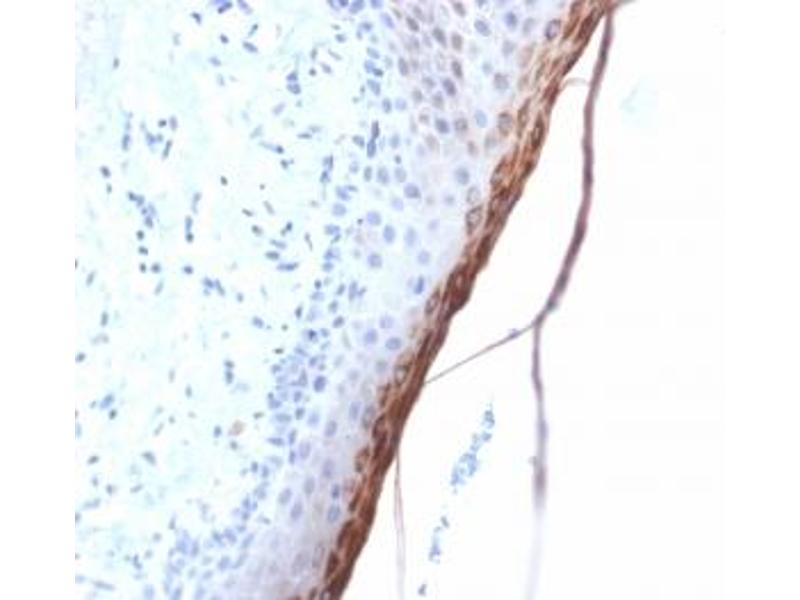

L’anticorps anti-Filaggrin Monoclonal Lapin est utilisé pour la détection de Filaggrin dans des échantillons de Humain. Il a été validé pour IHC (p).

Immunohistochemistry (Paraffin-embedded Sections) (IHC (p))

Amino acids 198-288 of human Filaggrin were used as the immunogen for this recombinant FLG antibody.

1. The prediluted format is supplied in a dropper bottle and is optimized for use in IHC. After epitope retrieval step (if required), drip mAb solution onto the tissue section and incubate at RT for 30 min.\. Immunohistochemistry (FFPE): 0.5-1 μg/mL for 30 min at RT,Prediluted IHC only format : incubate for 30 min at RT (1)

Filaggrin (FLG) is an intermediate filament-associated protein that aggregates keratin intermediate filaments in mammalian epidermis. It is initially synthesized as a polyprotein precursor, profilaggrin (consisting of multiple Filaggrin units of 324 aa each), which is localized in keratohyalin granules, and is subsequently proteolytically processed into individual functional Filaggrin molecules. Active Filaggrin is present at a level of the epidermis where keratinocytes are in transition between the live nucleated granular layer and the anucleate cornified layer, suggesting that filaggrin aids in the terminal differentiation process by facilitating apoptotic machinery.